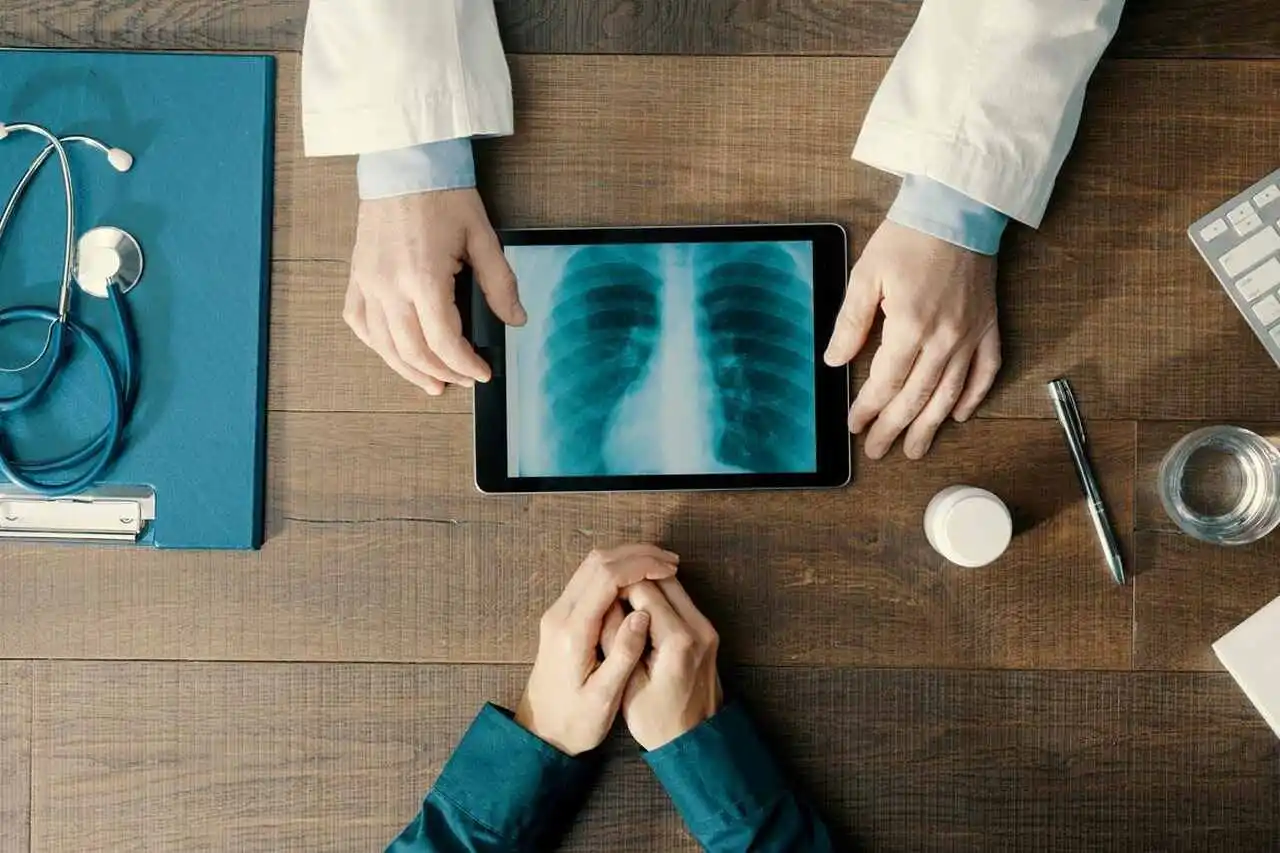

¿Cómo se diagnostica el cáncer de pulmón?

El diagnóstico del cáncer de pulmón comienza con la atención a los signos corporales, seguido de una consulta con un médico general, quien puede derivar al paciente a un neumólogo o un oncólogo.

Se solicitan pruebas de laboratorio y de imágenes, junto con biopsias de pulmón para confirmar la presencia de la enfermedad.

La estadificación del cáncer se realiza para determinar la localización y extensión de la patología, orientando la elección del tratamiento adecuado para cada caso.